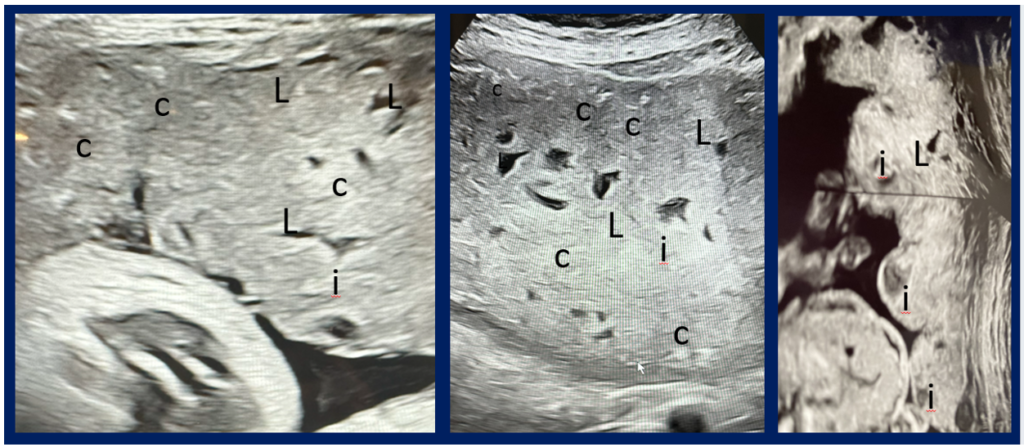

COVID-19ワクチンを妊娠中に接種した場合の安全性について、VAERS(米国ワクチン副作用報告システム)データを用いて、インフルエンザワクチンや他ワクチンと比較して評価した。妊娠関連の37種類の有害事象(流産、胎児奇形、胎盤異常、早産、死産など)を分析したところ、すべての項目でCDC/FDAの安全シグナル基準を超過しており、統計的有意差は非常に高かった。(多くが p < 0.001)COVID-19ワクチンは、新生児死亡、胎盤障害、胎児発育不全、早産、など多くの妊娠合併症と関連している可能性がある。妊娠中のCOVID-19ワクチン接種は重大な安全シグナルを示している。妊娠中の接種を世界的に停止すべきと提言。(2025, Thorp)

妊娠中にCOVID-19ワクチンを接種した後に観察された典型的な特徴を記録した、妊娠期の第3期における3つの別々の妊婦の超音波画像が描かれています。これらの所見の多くは、本報告における妊娠中のCOVID-19ワクチンに関連する複数の妊娠有害事象と一致しており、胎盤石灰化、胎盤不全、胎盤梗塞、胎盤血栓症、胎盤沈着、胎盤障害、羊水量減少、胎児成長制限が含まれます。画像は石灰化(c)、ラクナエ(L)、および梗塞(i)を表しています。